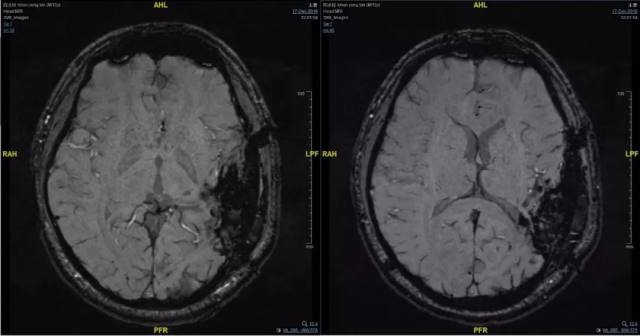

5、术后影像

6、病理

送检脑组织中可见畸形的血管成分,伴出血及血栓形成、机化,局灶可见钙化,伴多量含铁血黄色沉积,符合脑血管畸形,请结合临床。

免疫组化结果:CD31(血管+)、CD34(血管+),GFAP(+),CD68(局灶+),Ki-67(约 2%+)